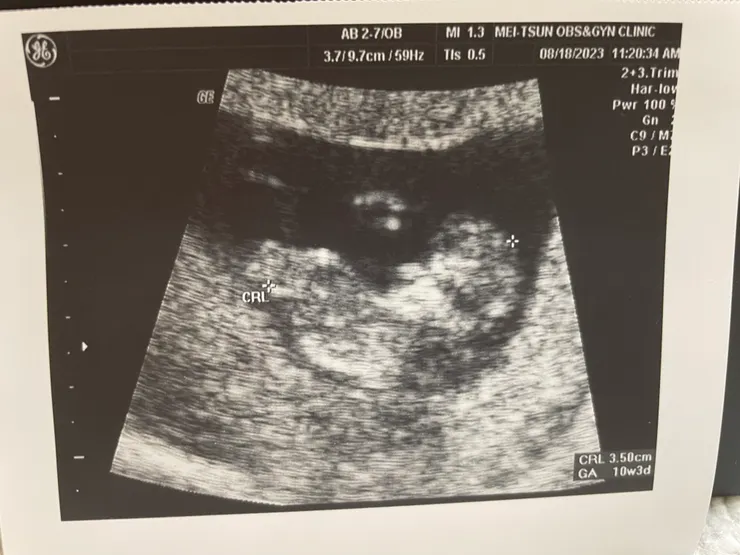

10W+3

不過好事是多見小福氣一次,乖乖長大!

第10週的驗血,數值正常,於是醫生建議可以拉長抽血時間與慢慢減針觀察!